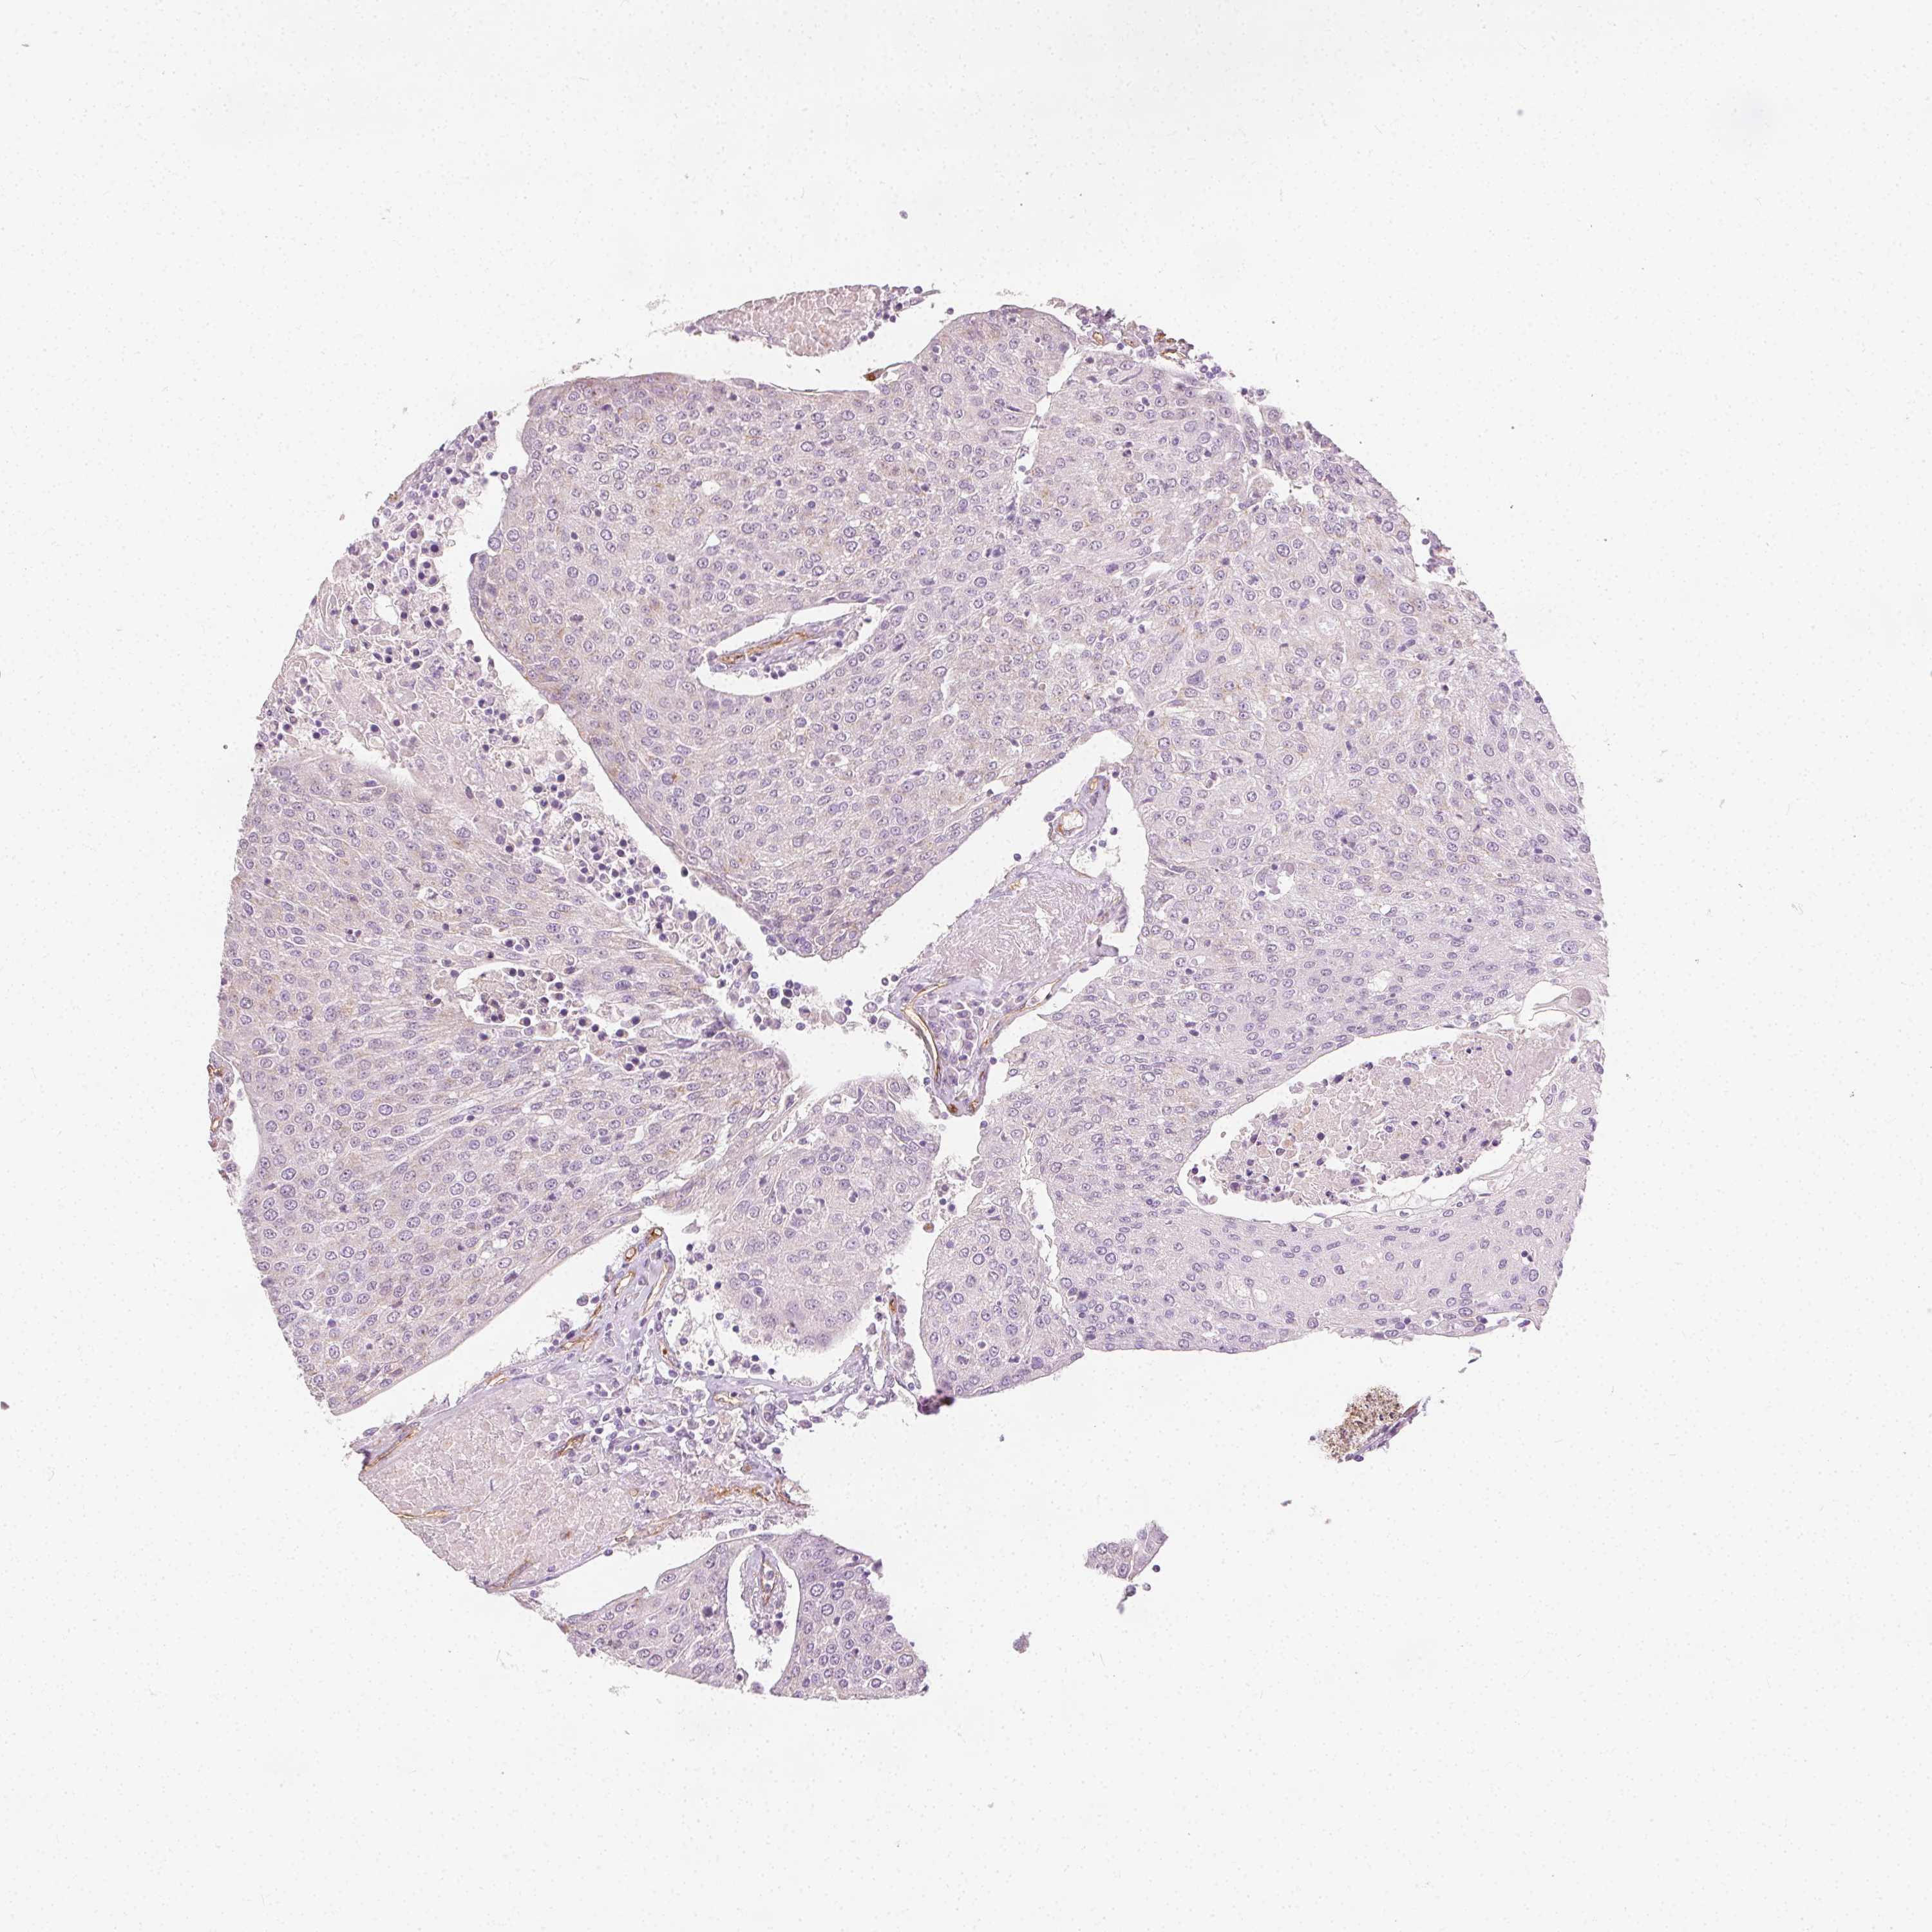

UROTHELIAL CANCER - Protein expressioni

A mouse-over function shows sample information and annotation data. Click on an image to view it in a full screen mode. Samples can be filtered based on level of antibody staining by selecting one or several of the following categories: high, medium, low and not detected. The assay and annotation is described here.

Antibody stainingi

Antibody staining in the annotated cell types in the current human tissue is reported as not detected, low, medium, or high, based on conventional immunohistochemistry profiling in selected tissues. This score is based on the combination of the staining intensity and fraction of stained cells.

Each image is clickable and will lead to virtual microscopy that enables deeper exploration of all samples and also displays staining intensity scores, fraction scores and subcellular localization as well as patient and tissue information for each sample.

HPA002110

HPA045507

CAB016169

CAB062558

CAB068219

CAB068220

Staining

High

Medium

Low

Not detected

Intensity

Strong

Moderate

Weak

Negative

Quantity

>75%

75%-25%

<25%

None

Location

Nuclear

Cytoplasmic/membranous

Cytoplasmic/membranous,nuclear

Urothelial carcinoma, High grade

Urothelial carcinoma, NOS

Urothelial carcinoma, Low grade